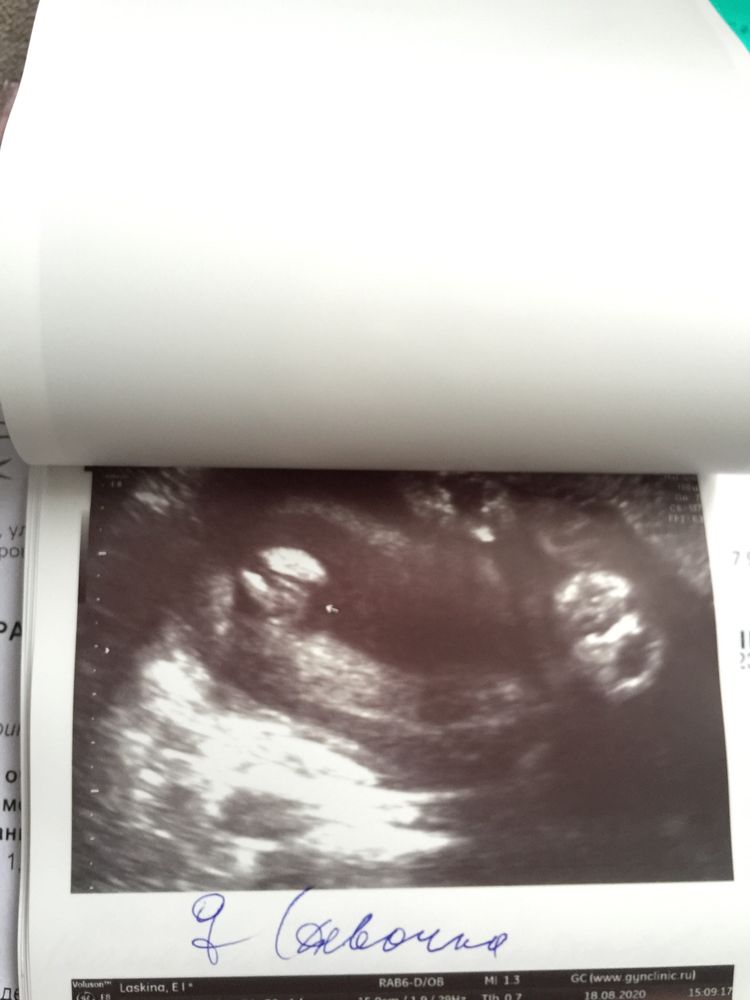

Только такое в наличии, около этих сроков.

От 20+ недель уже прям отчетливо было видно.